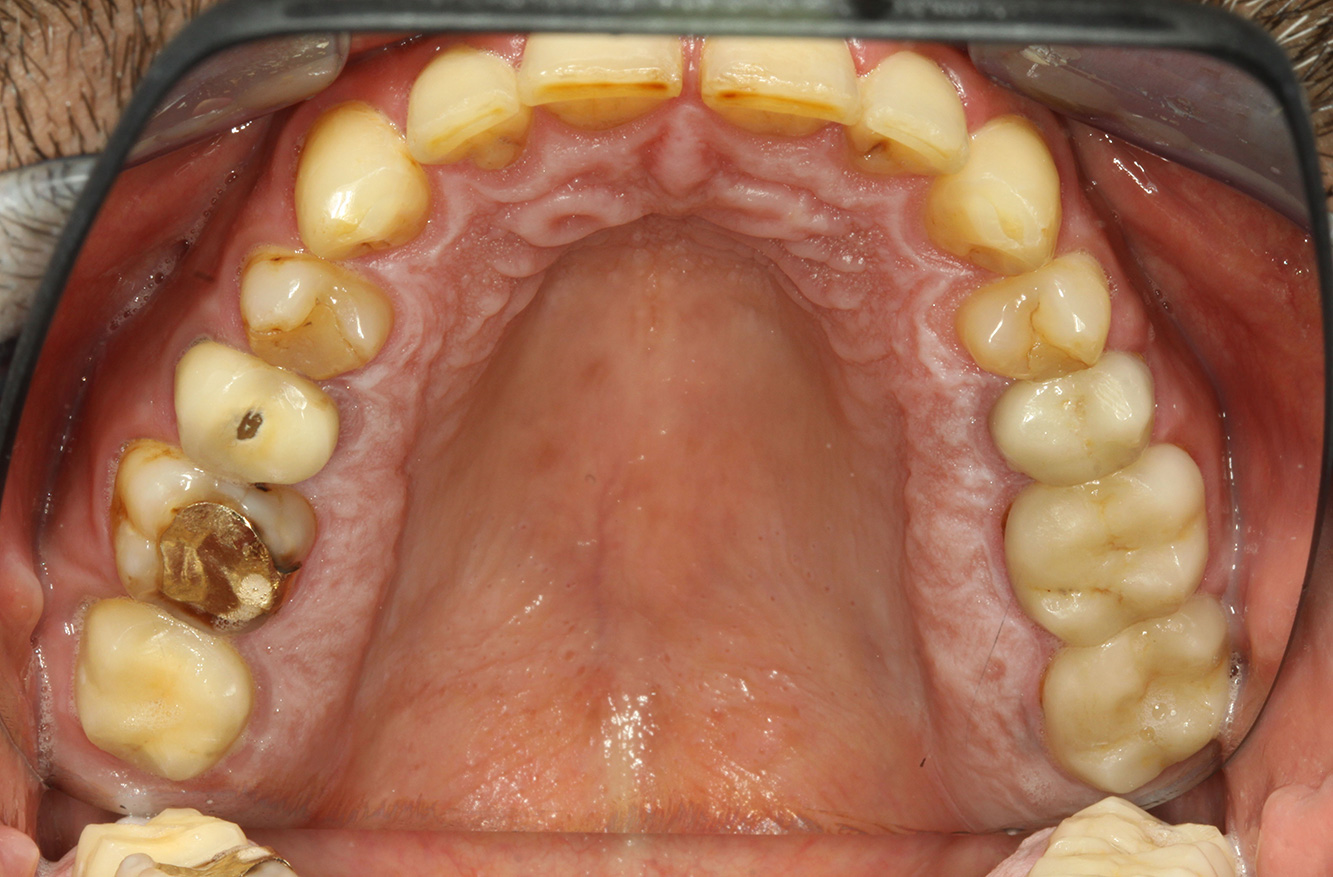

Der Endokarditis-Patient mit aktiven Kariesläsionen*

Der Patient ist 39 Jahre mit Z.n. Herzklappenersatz wegen Klappenfehlers und Endokarditis. Als Antikoagulans (Gerinnungshemmer) wird regelmäßig ASS 100 eingenommen. Aus dem Bereich Lebensstil ist die Ernährungsweise als kariesfördernd einzustufen, da mit hoher Regelmäßigkeit zuckerhaltige Lebensmittel sowie sechs bis sieben Mahlzeiten täglich verzehrt werden. Die Mundgesundheit des Patienten zeigt ein mittleres Kariesrisiko mit aktiven Läsionen. Das Parodontitisrisiko ist niedrig, es besteht eine Gingivitis. Es ergeben sich folgende Empfehlungen für die Prophylaxebehandlung.

Für die Prophylaxesitzung lassen sich keine spezifischen Instrumentierungsempfehlungen ableiten. Durch den gezielten Einsatz von Pulverstrahl und rotierend Polieren können Plaque und Verfärbungen an den Restaurationsrändern schonend entfernt und Wiederbesiedlungsnischen für kariogene Bakterien reduziert werden (19).

Zur weiteren Unterstützung der Kariesprävention ist eine Fluoridierung, besonders um der Neuentstehung im Bereich der Restaurationsränder vorzubeugen, und eine Versiegelung der Wurzeloberflächen empfehlenswert. Beide Maßnahmen können die angegebene Temperatursensibilität der Zähne reduzieren.